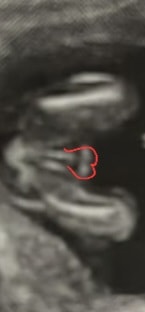

По моему, мошонка это. А пенис наверх смотрит, наверное. Но это я так вижу.

Жужу, да ну, явно же видно "кофейное зернышко". А вот на вашем снимке вижу прям мошонку)

Просто это может быть мошонка, а пенис вверх смотреть. У моей прям хорошо видно было, что половые губы и клитор,но и узи было в 20 нед., а тут я сразу подумала - мошонка...